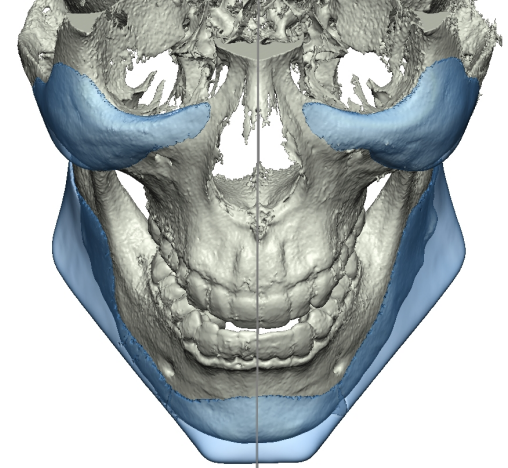

Recently got this implant design from Dr. Y for custom mandible (jaw & chin) and malar / cheekbones with infraorbital rims.

Interested in thoughts.